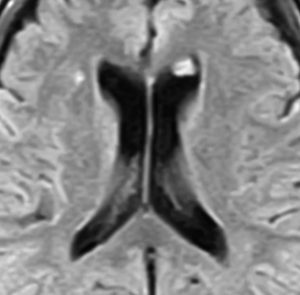

片側性水頭症

左尾状核から発生したものです。モンロー孔を閉塞して,片側性水頭症となっています。腫瘍がトリュフみたいにゴツゴツしているのも特徴です。

下のガドリニウム増強T1では,部分的に増強されます。

もちろん無症状ですが,年齢が若かったので全摘出しました。